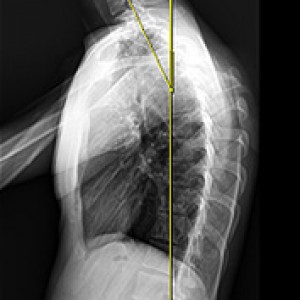

Before & After

해당 사진은 수정없는 실제 치료사진입니다.

환자의 치료결과는 환자의 상태, 치료방법 등에 따라 차이가 발생할 수 있습니다.